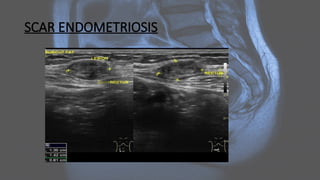

SCAR ENDOMETRIOSIS

Endometriosis • Endometriosis isa common, chronic gynecological condition defined as the presence of functional endometrial glands and stroma-like lesions outside the uterus. It manifests in three ways: superficial (peritoneal) disease, ovarian disease (endometriomas), and deep endometriosis. • Endometriosis is highly associated with adenomyosis (in which endometrial tissue is confined to the uterine musculature). Size varies, ranging from microscopic endometriotic implants to large cysts (endometriomas) and nodules. Deep infiltrating endometriosis is complex and surgically challenging.